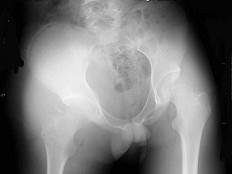

问题 18岁男性患者右髋关节进行性肿胀,疼痛1个月余,曾拟为“化脓性关节炎”,经抗炎治疗,症状无明显好转,右髋关节正位片如图所示,最可能的诊断是 ( )

选项 A、右髋关节化脓性关节炎 B、右髋关节Ewing肉瘤 C、右髋关节滑膜肉瘤 D、右髋关节纤维肉瘤 E、右髋关节软骨肉瘤

答案 C